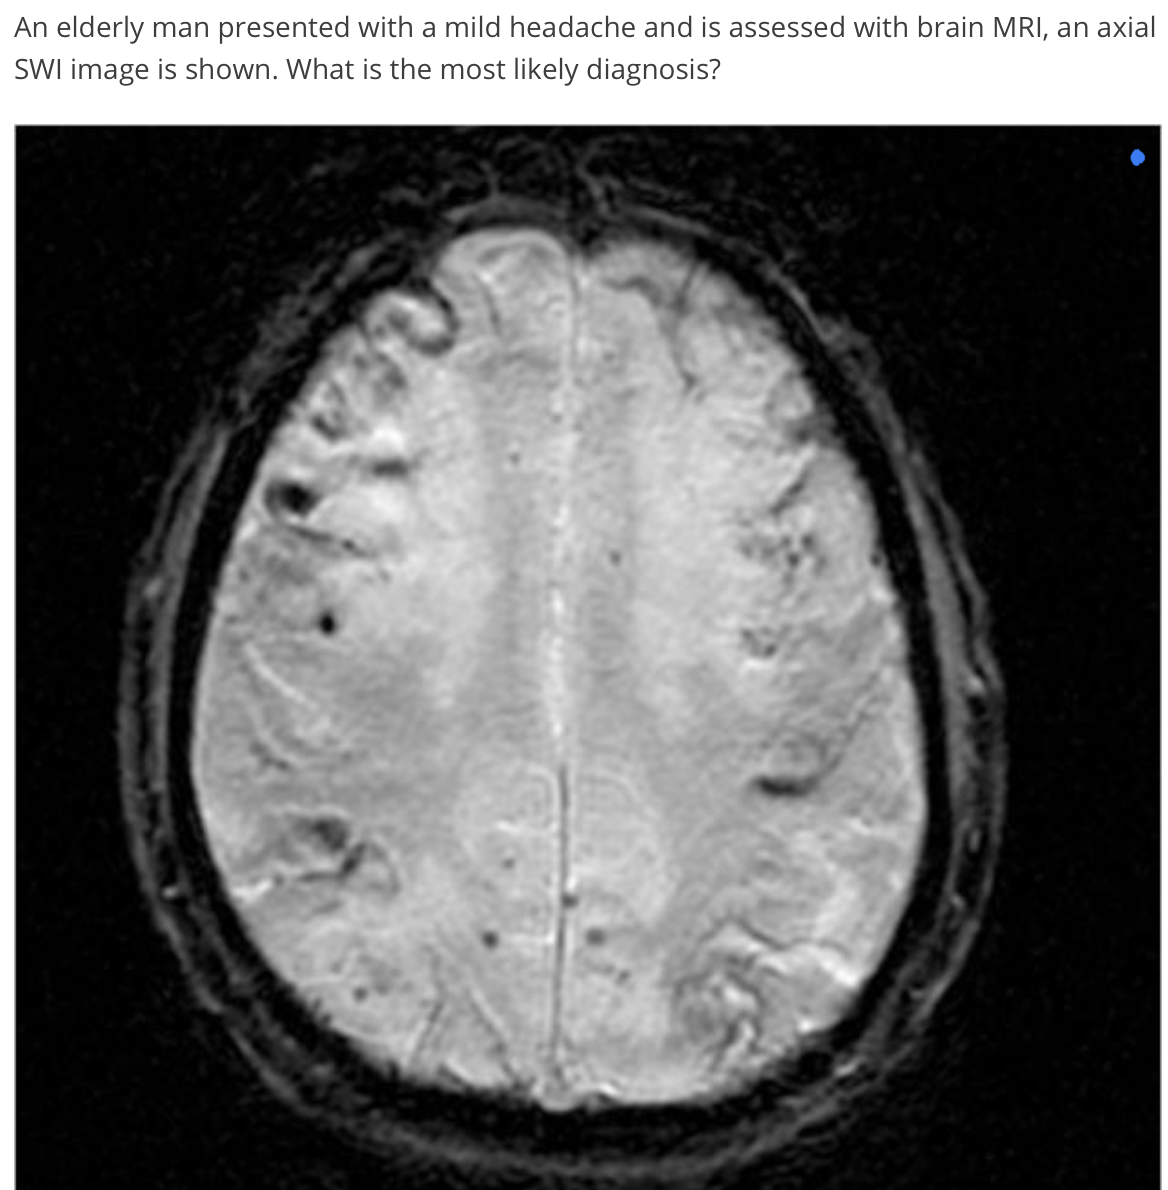

ICH

-swi in hyperacute/acute hematoma?

-swi- hematoma vs calcification